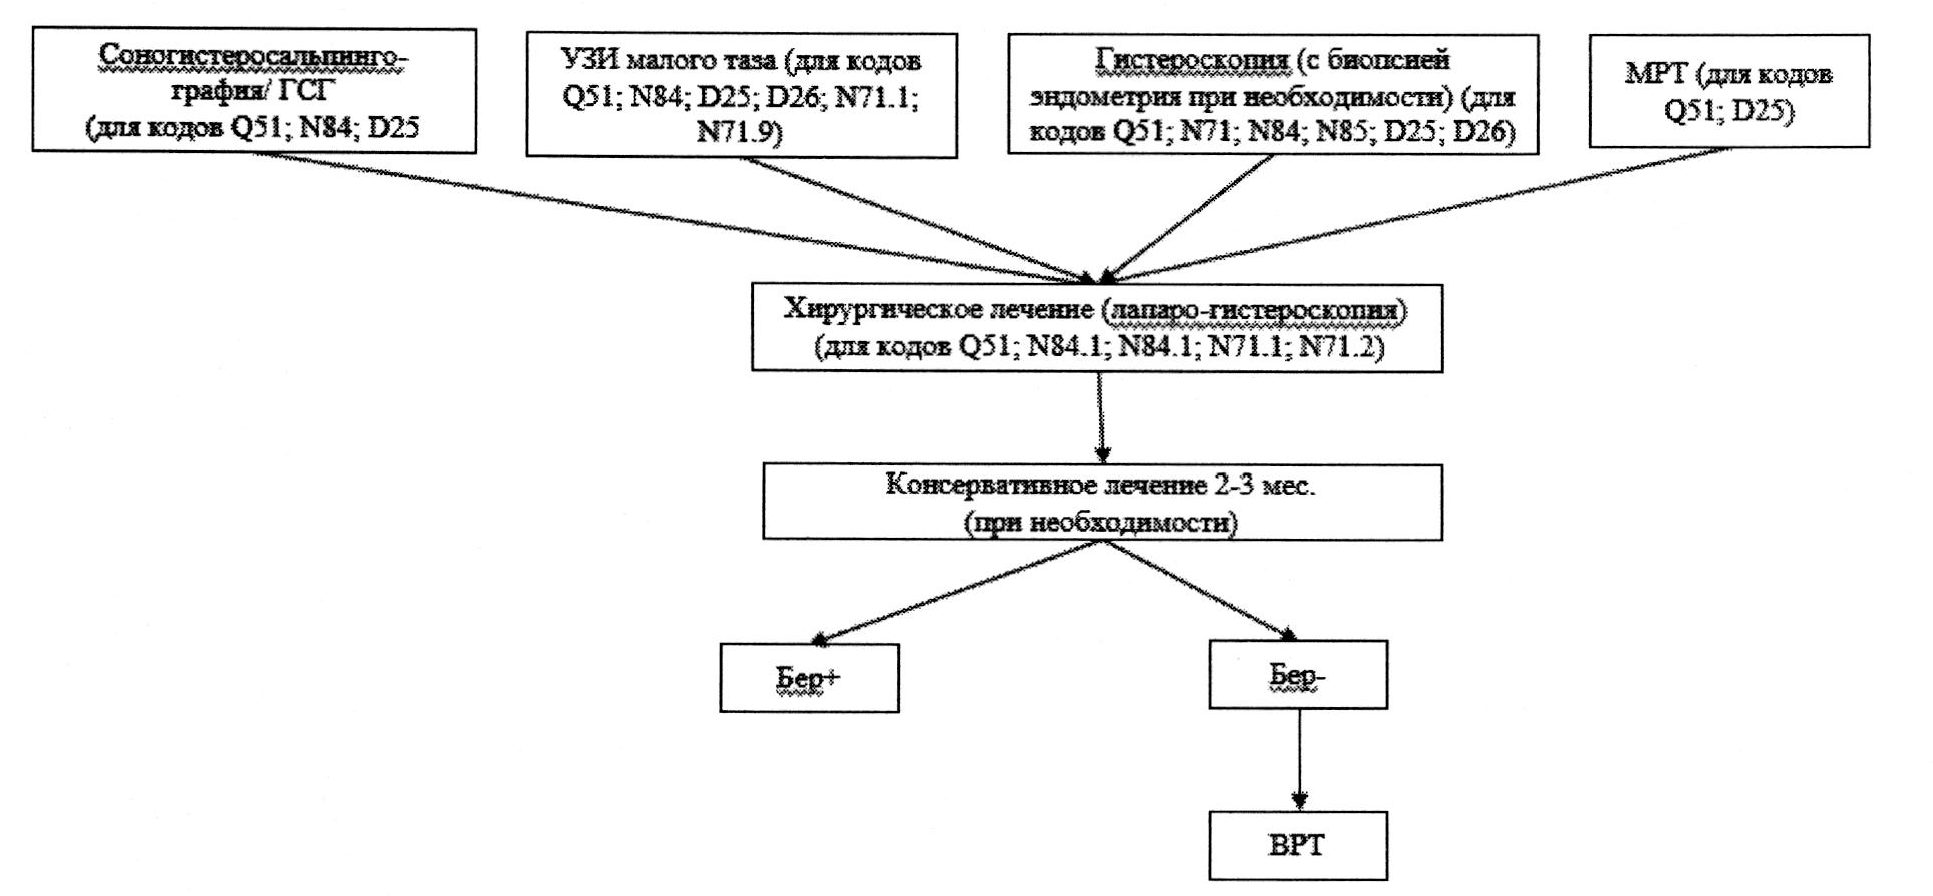

6. Женское бесплодие маточного происхождения (MKБ-10/N97.2)

Определение. Патологический процесс, нарушающий анатомо-функциональное состояние матки и процесс имплантации. Определение включает врожденные аномалии развития матки, отсутствие матки и приобретенные поражения матки, нарушающие процесс имплантации.

Этиология и патогенез. Врождённые аномалии матки формируются в результате воздействия различных повреждающих факторов на этапах эмбрионального развития (или антенатально). Приобретенные поражения матки возникают как следствие перенесенных ВЗОМТ, изменения гормонального гомеостаза, хирургических манипуляций на матке.

Эпидемиология. В структуре причин женского бесплодия частота маточного фактора составляет около 50% [50].

По МКБ-10 объединяет коды:

Q51 - врожденные аномалии половых органов;

Q51.1 - удвоение тела матки с удвоением влагалища и шейки матки;

Q51.2 - другие удвоения матки;

Q51.3 - двурогая матка;

Q51.4 - однорогая матка;

N71.1 - хроническая воспалительная болезнь матки;

N71.9 - воспалительная болезнь матки неуточненная;

N84.0 - полип тела матки;

N84.1 - полип шейки матки;

D25 - лейомиома матки;

D26 - другие доброкачественные новобразования матки;

N85.6 - внутриматочные синехии.

Диагностика

Жалобы и анамнез. Рекомендуется при опросе пациентки особенно обращать внимание на наличие маточных кровотечений, перименструальных и межменструальных кровянистых выделений, болевого синдрома, ранее перенесенных ИППП, внутриматочных манипуляций.

Инструментальная диагностика:

- УЗИ органов малого таза (для кодов Q51; N84; D25; D26; N71.1; N71.9);

- гистероскопия (с биопсией эндометрия при необходимости) (для кодов Q51; N71; N84; N85; D25; D26);

- соногистеросальпингоскопия (для кодов Q51; N84; D25);

- ГСГ (для кодов Q51; N84; D25);

- МРТ (для кодов Q51; D25).

Лечение

- Метод достижения беременности 1-й линии - хирургическое лечение (лапаро-гистероскопия) (для кодов Q51; N84.1; N84.1; N71.1; N71.2).

- Выбор и объем хирургического пособия определяется особенностями патологических изменений матки и ее полости.

- Консервативное лечение оправдано после проведения хирургического вмешательства только в качестве компонента комплексного восстановительного лечения, для улучшения условий наступления беременности.

- Лечение в программах ВРТ - при отсутствии внутриматочной патологии.

период времени для ожидания наступления беременности после операции на матке - не более 1 года при условии проходимости маточных труб, сохраненной овуляции, нормальном овариальном резерве и отсутствии мужского фактора бесплодия;

при отсутствии хотя бы одного из этих условий показано направление для лечения в программах ВРТ по окончанию восстановительного периода после операции, определяемого видом и объемом хирургического лечения.

Операции при маточной форме бесплодия: